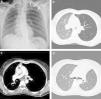

a) Chest radiograph showing a left side pneumothorax (arrows). b) Chest CT showing increased left lung volume with contralateral mediastinum shift and decreased ipsilateral lung attenuation. c) Chest CT showing a 2 cm lesion in the left main bronchus. d) Chest CT, eighteen moths after surgery, showing resolution of the mediastinum shift and similar bilateral lung attenuations.

We report the case of a 30-year-old woman who presented to the emergency department of our hospital center with complaints of a recent left side pleuritic chest pain and a history of cough over the past 2 months. She was a non-smoker. Physical examination and chest radiograph indicated a left side pneumothorax (Fig. 1a). An intercostal tube was inserted; the lung fully expanded without any detectable air-leak and the chest tube was removed. At discharge the patient was asymptomatic and chest radiograph showed no abnormalities. Two months later she returned with new onset hemoptysis. Chest radiograph showed a small left side pneumothorax and increased ipsilateral lung volume with a contralateral mediastinum shift, both of which increased with expiration. A chest computed tomography (CT) confirmed these alterations with significantly decreased ipsilateral lung attenuation and showed a 2cm lesion in the left main bronchus (Fig. 1b and c). Bronchoscopy showed a cherry red polypoid tumor, easily hemorrhagic, causing an almost total obstruction of the left main bronchus. Biopsy of the tumor indicated a typical carcinoid tumor. An octreotide scan revealed uptake solely in the lesion of the left main bronchus and so a sleeve-type surgery was performed with excision of the main bronchus and lobectomy of left upper lobe. Histological examination confirmed a typical carcinoid tumor of the left main bronchus and showed no signs of emphysema or pleural blebs. The post-surgical period was insignificant and the patient was discharged home. Eighteen months after surgery she is asymptomatic, had no new pneumothoraces and her chest CT shows resolution of the mediastinum shift and similar bilateral lung attenuations (Fig. 1d).